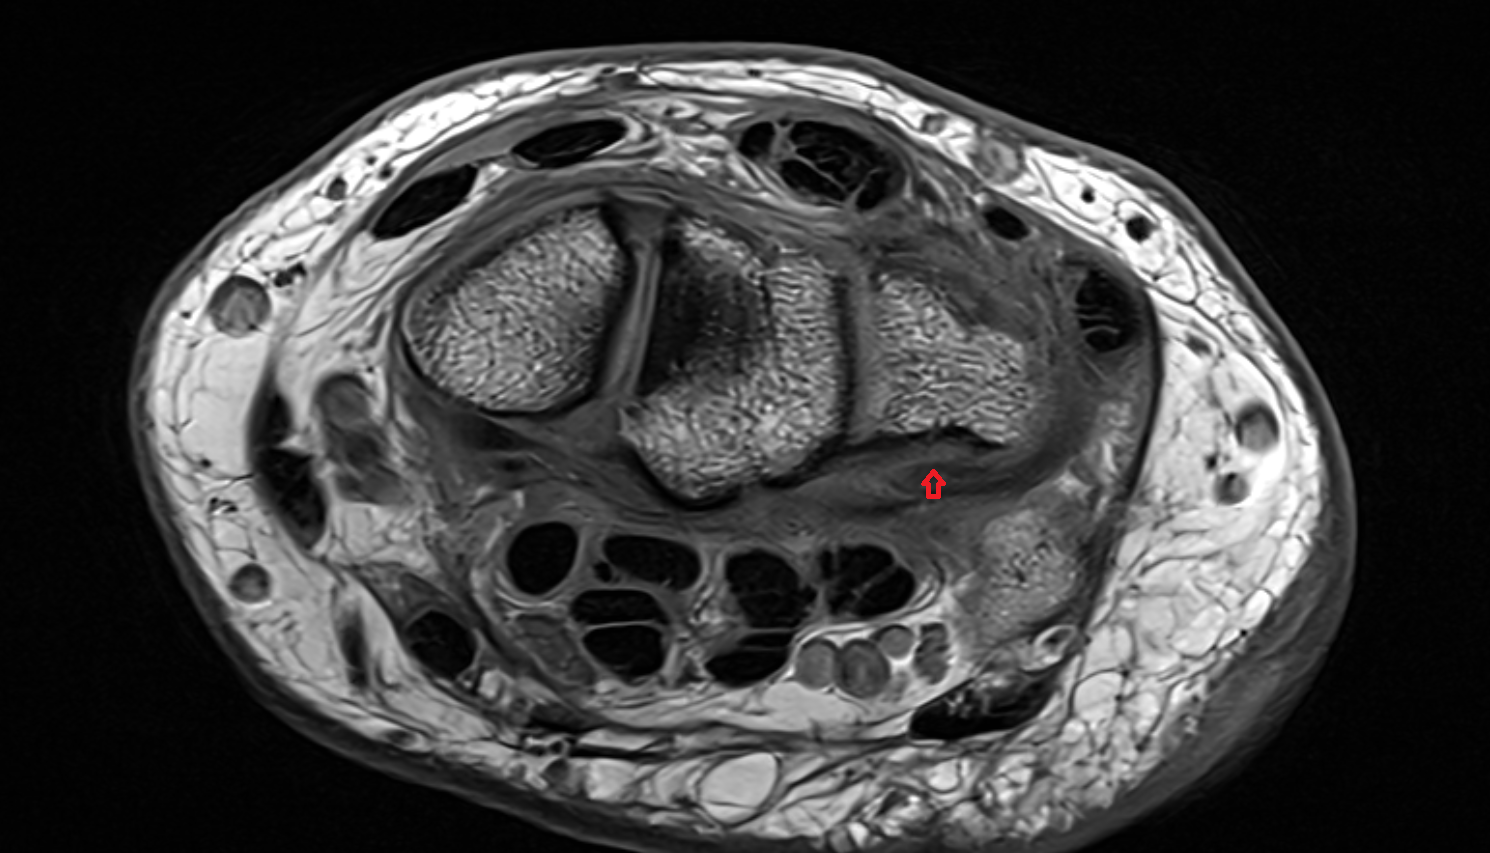

- Meniscus cartilage

- Medial meniscus

- Lateral meniscus